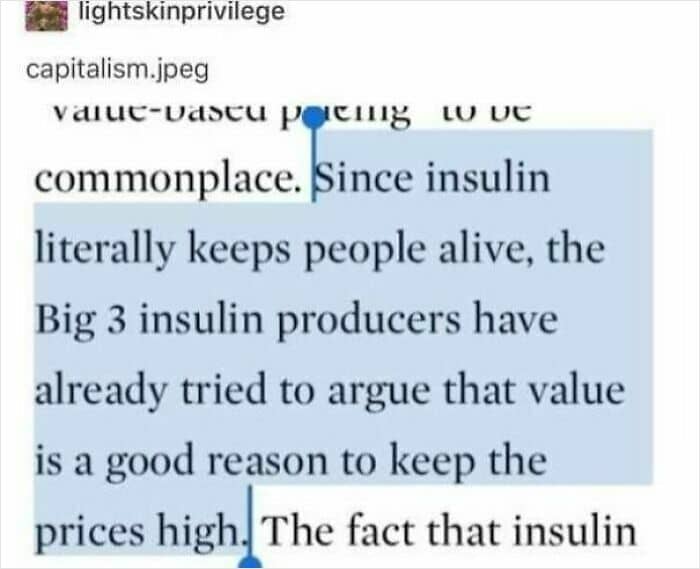

#1 Capitalist Innovation

#2 Dentist Office Charged My Sister $500 For A CT Scan They Never Performed